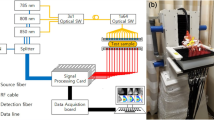

DOT was performed on a Philips diffuse optical tomography system (Philips Healthcare, Best, The Netherlands). A patient was placed in the prone position on the system bed with her breast suspended in a cup on which 507 optical fibers are mounted (Fig. 1). The 253 source fibers are connected to four continuous wave solid-state lasers (wavelengths 690, 730, 780, and 850 nm) and interleaved with 254 detector fibers. The cup was filled with a matching fluid, which has optical properties similar to an average breast, to enable a stable optical coupling between fibers and breast, and to eliminate optical shortcuts around the breast. During imaging, the breast was sequentially illuminated from all source positions and light emanating from the breast was detected in parallel for each source position. Acquisition duration was approximately 1 min per wavelength per breast, leading to a total examination time of approximately 10 min per patient. After optical data acquisition, three-dimensional absorption images were reconstructed for each wavelength by using a linear reconstruction algorithm based on the Rytov approximation [9].